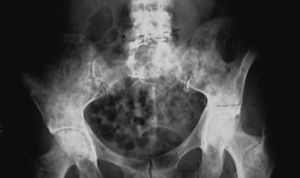

在病變部骨質呈大塊溶骨性骨質吸收,骨幹變細,皮質變薄。大塊骨質吸收後呈現骨質缺損,殘端呈尖削狀。有殘存疏鬆的萎縮骨,無新生骨,無骨膜反應,無軟組織腫塊。

3、神經性關節病的X線表現分3 型:吸收型、增生型及混合型,而且以增生型及混合型更多見,多數病例表現骨質增生明顯,伴有骨膜反應,關節畸形,關節面不規則、塌陷,關節間隙變窄。而骨溶解症X線表現:早期病變多侵犯單一骨骼,隨著病程發展病變範圍逐漸擴大,直至同一解剖部位的骨骼全部溶解吸收,並發生病理性骨折。早期骨皮質下及髓腔內有透亮區,繼而皮質骨向中心皺縮,最後骨質完全溶解破壞。受累骨質無骨膜反應,無新生骨形成。